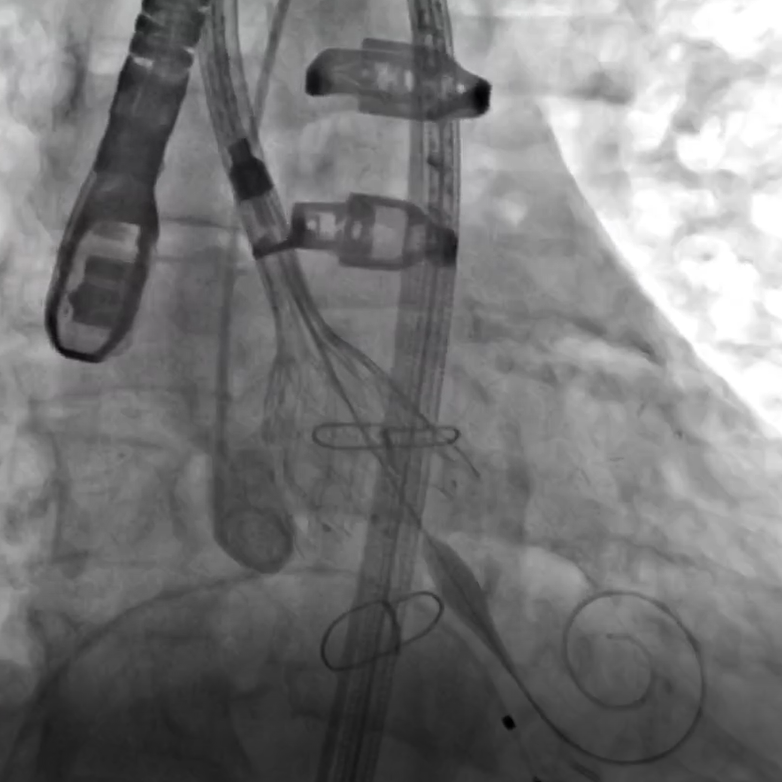

患者在全麻下进行手术,经右侧股动脉建立主入路,直头导丝跨瓣后交换预塑弯形导丝放置于左室。TaurusMax®经导管主动脉瓣系统装载AV29瓣膜,该系统具有“双轴”调弯功能,系统过弓跨瓣更加安全顺畅,同时系统在跨瓣后可实现同轴调整,降低术中对导丝操作的依赖,改善瓣膜释放不同轴导致的高低瓣问题,提升瓣膜释放稳定性及血流动力学。瓣膜在调弯状态下一次释放脱钩,瓣膜深度瓣下2mm,形态良好,同轴性佳,DSA下对合缘对齐(CA)结果良好。

术中影像

调弯过弓并跨瓣

跨瓣后T-Marker方向检查

通过显影点初步判断CA&辅助判断深度

调弯状态下稳定脱钩释放